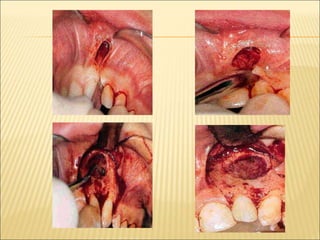

SURGICAL TECHNIQUE

 Anaesthesia

 Aspiration

 Incisions – circular

oval

eliptical

inverted ‘u’

 Removal of bone

 Removal of cystic lining specimen

 Irrigation of cystic cavity

 Suturing

 Packing – white head’s varnish

tincture of benzoin

bismuth iodine paraffin

paste(BIPP)

 Maintenance

 Use of plug

 Healing

MODIFICATIONS OF MARSUPIALIZATION